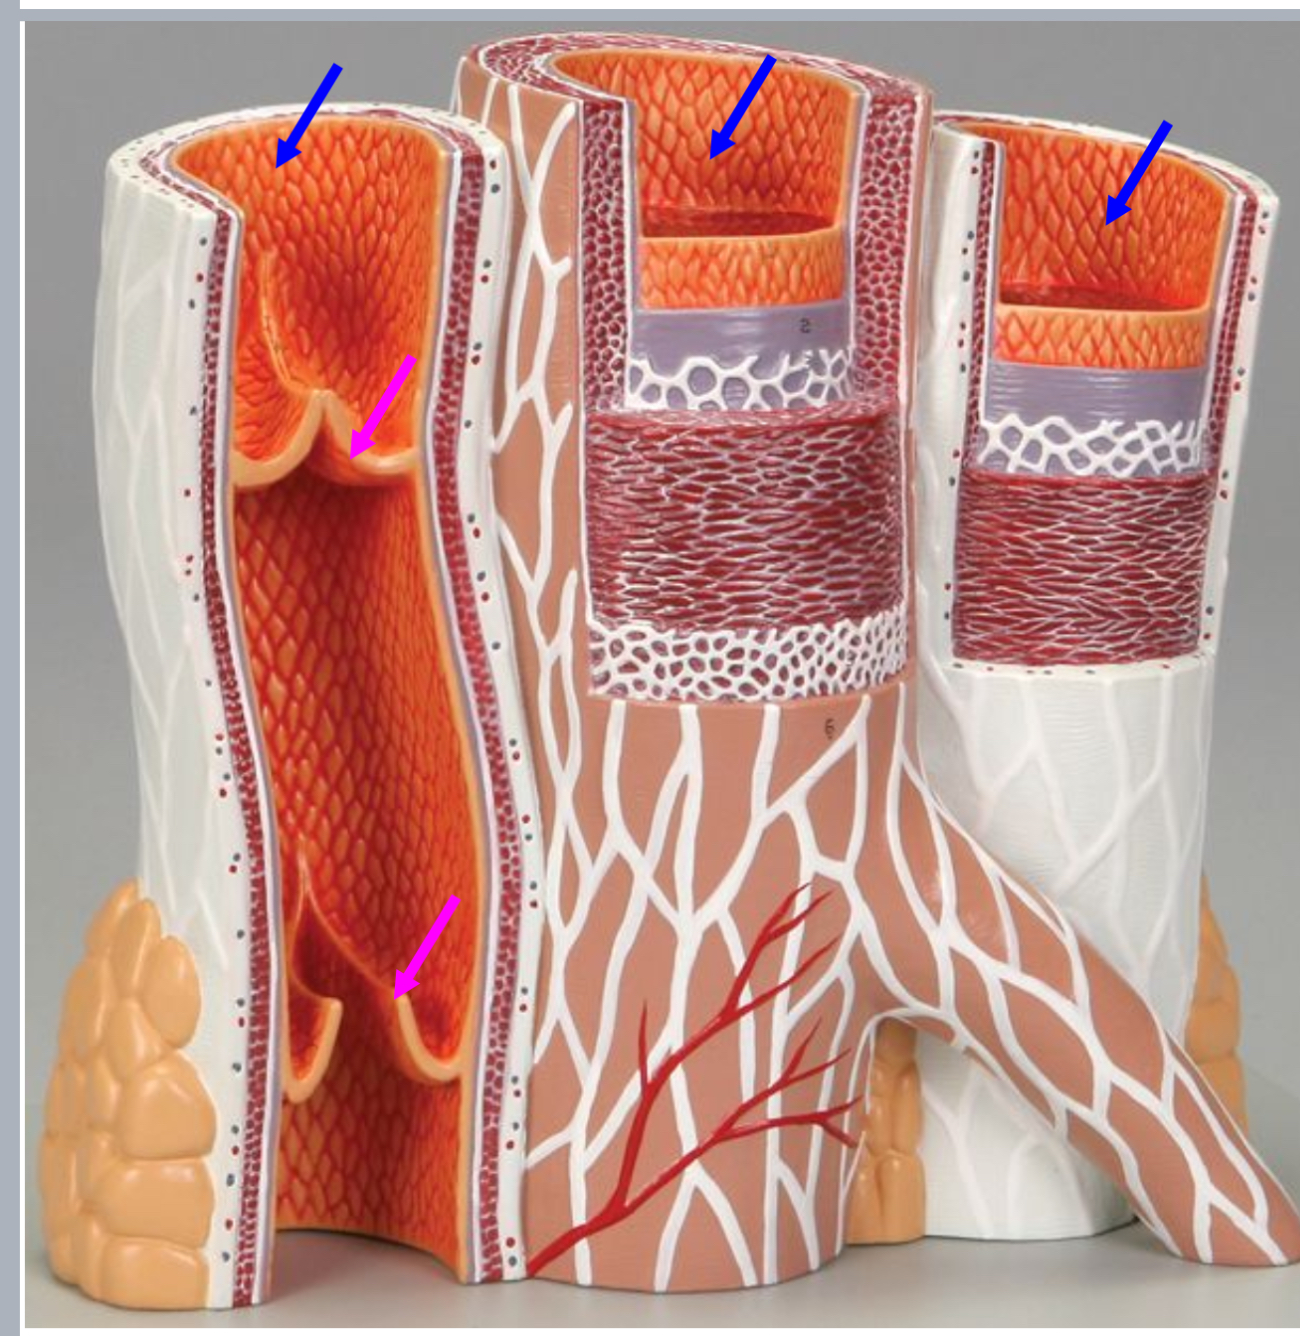

Tunica intima

Name the blue arrow

Lines lumen and release vasoactive chemicals

Function of tunica intima

Venous valves

Name the pink arrow

Prevent backflow of blood

Function of venous valves

Tunica media

Name green arrow

Vasoconstriction and vasodilation

Function of tunica media

Tunica externa

Name the purple arrow

Anchor and bind vessel

Function of tunica externa

Artery

Artery or vein?

Vein

Artery or vein?

Tunica intima

Name the green arrow

Tunica media

Name the yellow

Tunica externa

Name the black